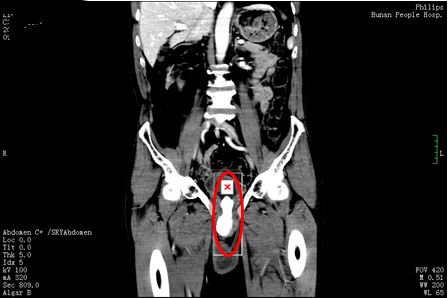

3月11日,刘先生在家人陪同下来到捷克论坛 泌尿外科门诊就诊,郭琼副主任医师接诊后,仔细询问病史并进行体格检查后发现,老人的左侧阴囊肿大,内有一个卵圆形的囊性肿块,符合“左侧睾丸鞘膜积液”的诊断。然而让医师惊讶的是,患者的绝大部分阴茎内都充满了坚硬的结节,压痛十分明显,高度怀疑是尿道结石。果然,泌尿系CT 检查发现,其膀胱尿道口和尿道内有一个鹅蛋大的结石,这正是导致老人持续会阴剧痛、尿频、尿急、排尿困难的罪魁祸首,随即将他收入泌尿三科病房。

郭琼副主任医师团队综合评估患者病情后,为他制定了“一石二鸟”的手术方案,一次手术同时解决尿道结石和睾丸鞘膜积液两个问题。322日,手术团队在全麻下为刘先生施行“左侧鞘膜翻转、尿道切开取石、尿道修补、膀胱镜检查、膀胱造瘘术”。在患者的后尿道及部分前尿道取出约10×8.1×4.5cm3大小重达256g,形态不规则、质地坚硬的结石。手术过程十分顺利,术中几乎无出血。